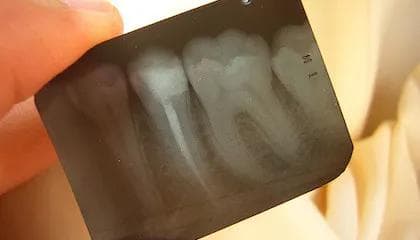

Som oftest er tannen blitt skadet på grunn av et stort kariesangrep eller en sprekk. Behandles ikke nerven som er skadet eller død, vil bakteriene spre seg til tannens rotspiss. Dermed vil det oppstå en betennelse i benet rundt rotspissen, som igjen fører til at en tannbyll dannes. Denne tannbyllen gir hevelse og kan også føre til en fistelåpning («kvise på tannkjøttet»). Betennelsen i nerven kan gi tannpine, eller være helt symptomfri slik at det oppdages ved et rutinemessig røntgenbilde.

Først vil nerven og bakterier fjernes inne i tannen. Kanalene hvor nerven har vært, renses ut og fylles så igjen med en masse. For å sikre at alle bakterier er borte, må et bakteriedrepende innlegg legges i tannen i en periode. Likevel kan det i noen tilfeller være slik at ikke alle bakterier blir borte. Da kan en kirurgisk fjerning av rotspissen være nødvendig. En rotfylling er en komplisert behandling som krever tid og presisjon. En tann har alt fra en til fire rotkanaler, og det kan bli mer tidkrevende jo flere kanaler tannen din har.